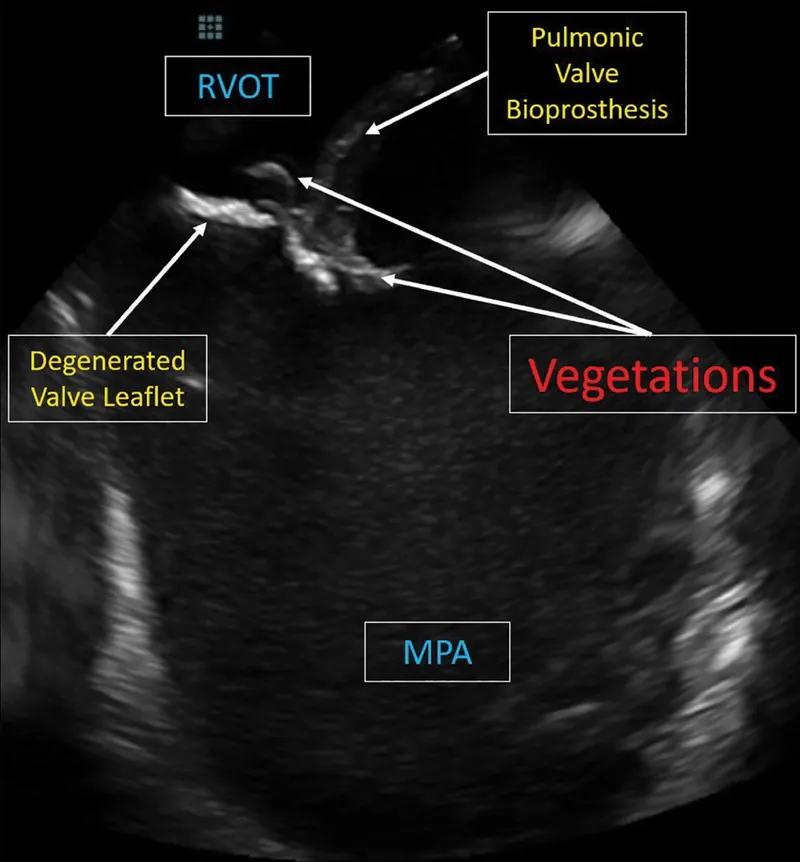

- Major: +ve Blood Culture (typical organism); Echo (vegetation, abscess, new regurgitation).

- Infective Endocarditis (IE): Diagnosis via Duke Criteria. Staph. aureus (IVDU, tricuspid), Viridans streptococci (post-dental).